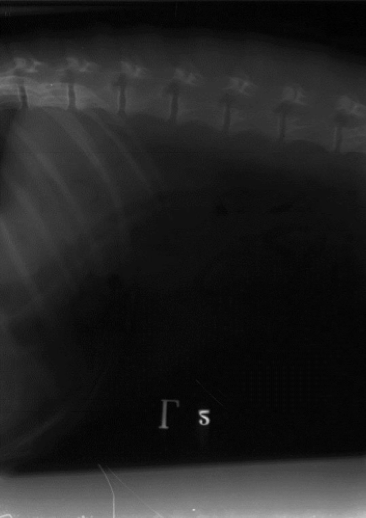

What is the issue with the developement of this film: